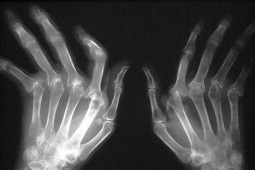

Potencjalne objawy prowadzące do RZS

Zachorowanie na RZS jest procesem wieloetapowym. U osoby predysponowanej pod wpływem czynników środowiskowych ma miejsce zainicjowanie procesu autoimmunologicznego będącego elementem patogenezy RZS. Kolejnym etapem jest okres występowania u chorego objawów chorobowych, ale jeszcze bez klinicznie wyrażonego zapalenia stawów (zapalenia błony maziowej). Właśnie ten etap rozwoju RZS wzbudza zainteresowanie reumatologów. Jak wskazują dotychczasowe dane, włączenie leków modyfikujących przebieg choroby (LMPCh) na wczesnym etapie choroby poprawia rokowanie, skraca czas do osiągnięcia remisji, a co więcej umożliwia uzyskanie również trwałej remisji. Koncepcja wytypowania wśród pacjentów z bólami stawów tych, którzy w przyszłości zachorują na RZS stała się podstawą projektu przeprowadzonego przez grupę ekspertów pod auspicjami EULAR.